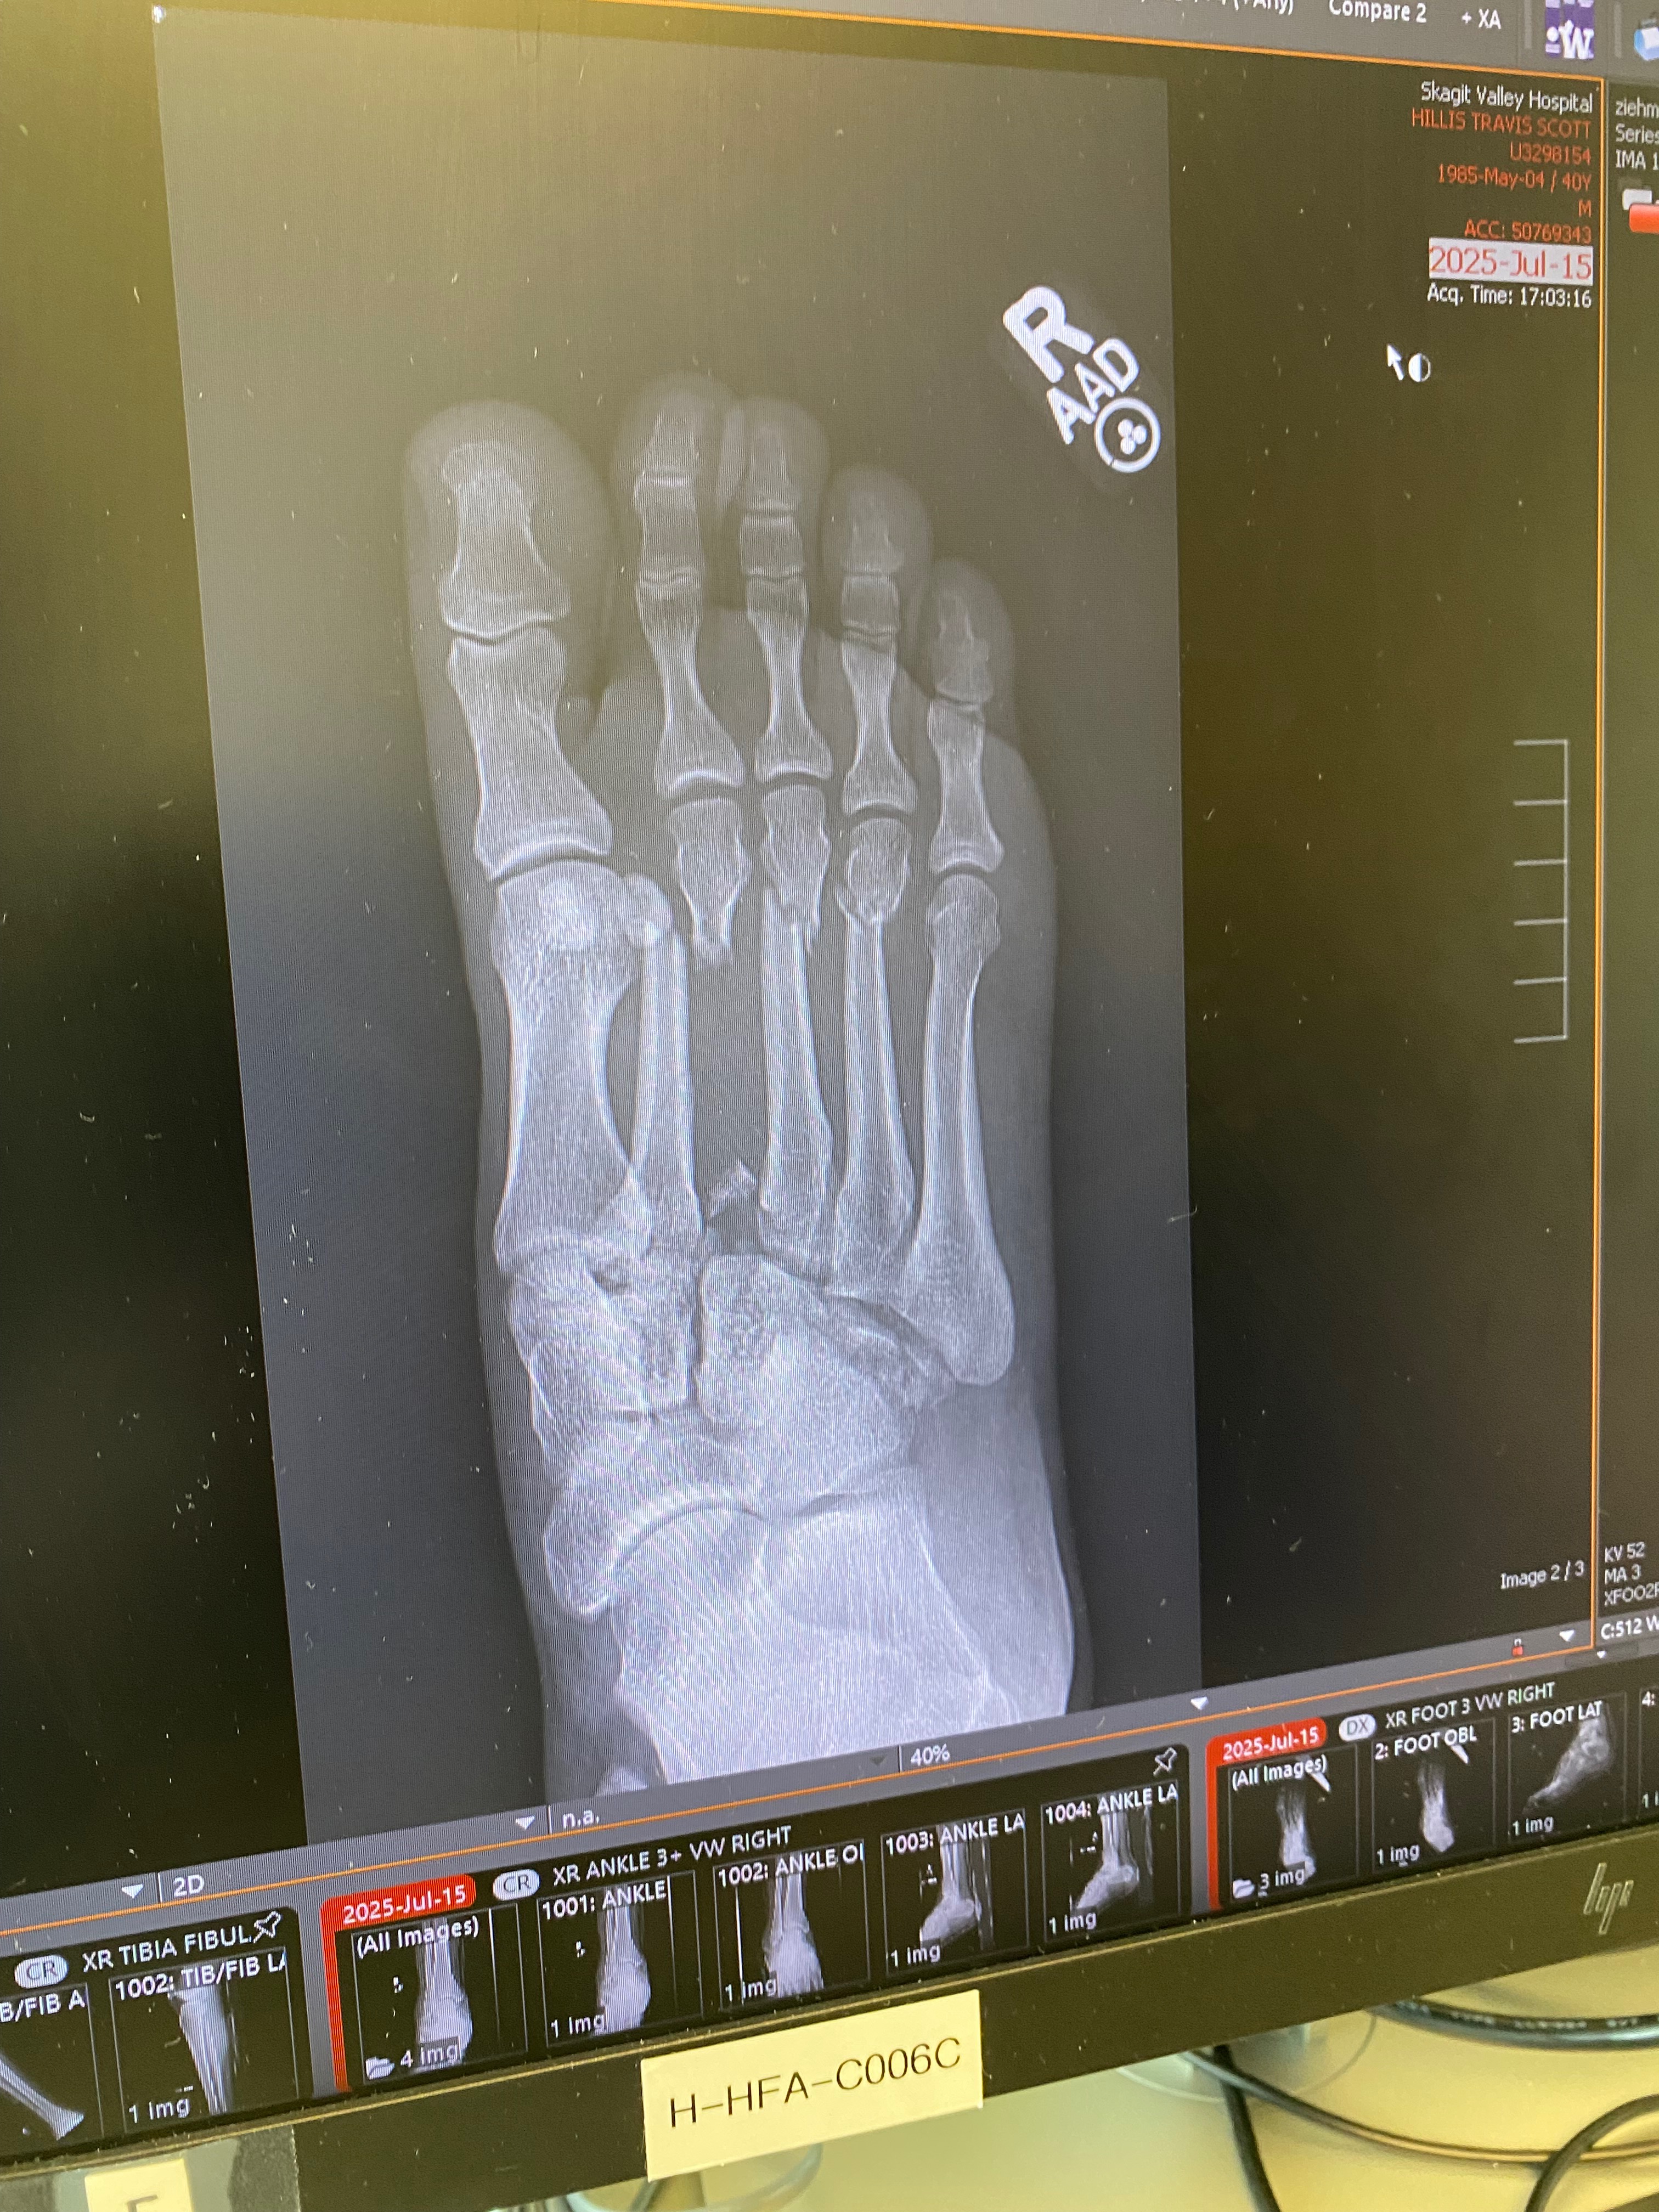

My name is Travis Hillis. In April, I was laid off from my job but was getting unemployment, which was better than nothing while I searched for new work. I found a job working with a friend of mine that I was going to start as soon as possible. Unfortunately, the week I was supposed to go in for paperwork to start work, on Tuesday, July 15th, I had a serious accident while riding a friend's quad in my field looking for a part that was lost from my kid's bike. I made one bad decision to hit the gas while turning to spin the back tires around. The tire caught in dry ground, causing the 700lbs quad to roll. I tried to jump clear of it but got my foot caught while the quad rolled over on top of me, shattering my right foot and breaking my right shoulder. I spent four days and three nights in the hospital before getting released until my second surgery on my foot.

Because of this extremely painful and unfortunate event, I no longer can work or qualify for unemployment, which means I now have zero income and bills stacking up. Just my surgery on Wednesday, 7/23 alone costs just over $70,000.